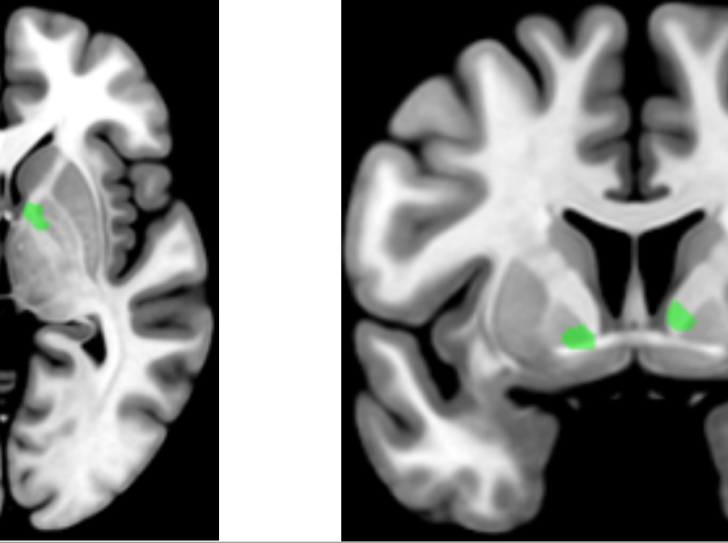

Manier des outils mécaniques améliore nos compétences langagières

Notre capacité à comprendre la syntaxe de certaines phrases complexes fait partie des compétences langagières les plus difficiles à acquérir. En 2019…